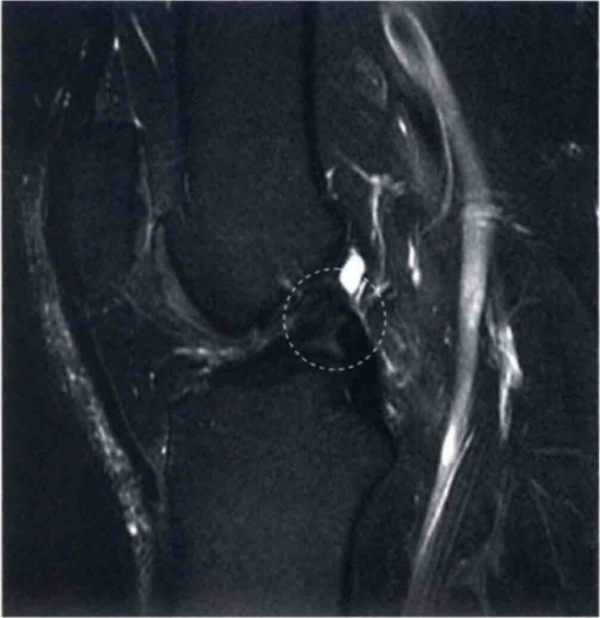

图5 显示了之前的ACL陈旧性损伤,随后瘢痕向下搭在PCL上(圆形区),并且在关节镜下证实